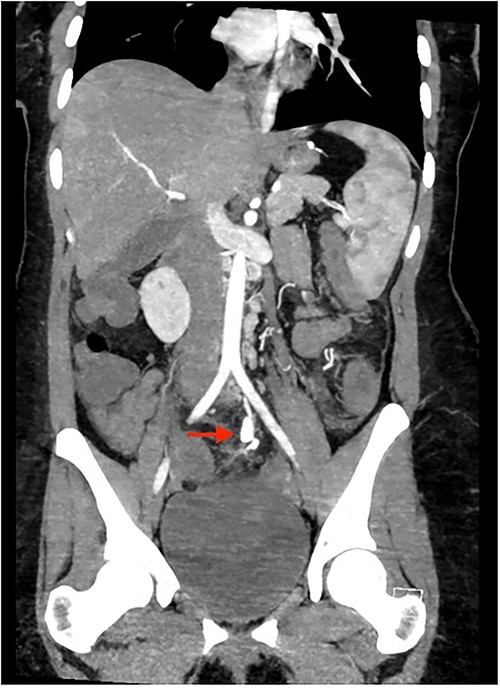

Colonoscopy showed an unremarkable rectal mucosa; however, starting in the sigmoid colon, there was diffuse circumferential ulceration and evidence of a necrotic mucosal lining (Fig. 1). The area was ulcerated and firm, extending from the sigmoid colon, through the descending colon, to the splenic flexure. Once at the splenic flexure, the remainder of the colon and terminal ileum were unremarkable for significant inflammation. These findings raised concern for ischemic-type injury rather than inflammatory bowel disease. A subsequent CTA was primarily notable for left colonic thickening, hypoenhancement, and multiple aneurysms and irregularities of the inferior mesenteric artery in a distribution concerning for vasculitis (Fig. 2). Rheumatological recommendations included a laboratory workup with: antinuclear antibody, antineutrophilic-cytoplasmic antibody, cytomegalovirus, histoplasma, treponemal, hepatitis panel, which all returned negative.

Colonoscopy: diffuse circumferential ulceration and a necrotic lining.